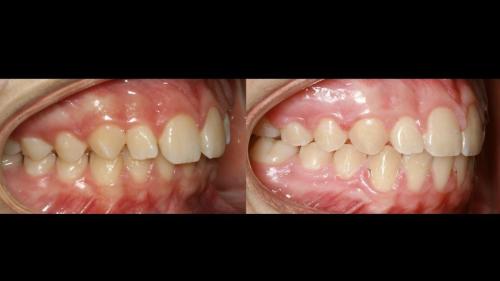

large-Resultados sin que se note ortodoncia

large-Resultados con balance

large-Ortodoncia Lingual

large-Resultado de avance de la mandibula

large-Ortodoncia lingual invisible

large-Lingual

large-Fractura con resina

large-Fractura

large-Combinacion con cirugia

large-Diapositiva14

large-Cambios en el perfil

large-Cambio magico

large-Cambio labial

large-Cambio en el perfil

large-Adultos -Se puede

large-Avance de mordida

large-Sonrisa en adulto

large-Sonrisa Adulto